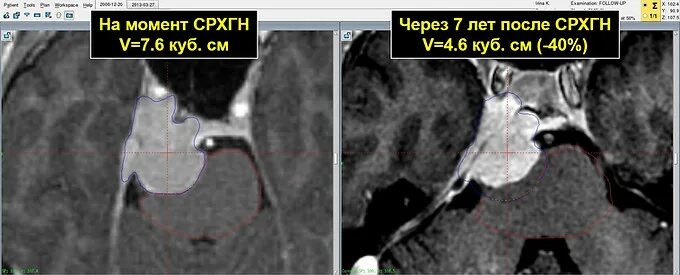

Менингиомы головного мозга мкб